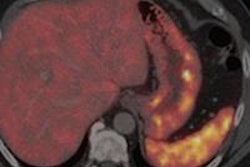

Left: Axial F-18 FDG PET uptake in the same patient is illustrated within the left cervical lymph node in keeping with increased glucose metabolic activity. Right: Coronal Dixon T1-weighted in-phase MR image with superimposed F-18 FDG PET uptake. Left cervical lymphadenopathy is demonstrated in a patient with a known diagnosis of Hodgkin's lymphoma.One of the first commercially available PET/MRI systems is from Siemens Healthcare, Biograph mMR. The scanner has a 60-cm bore and 3-tesla magnet that integrates a ring of solid-state PET detectors that are insensitive to magnetic fields, enabling the system to simultaneously acquire PET and MRI signals.

For lymphoma, increased glucose metabolism is common to most lymphoma subtypes, and PET with F-18 FDG has become an established method to stage lymphoma; a recent study demonstrated the feasibility of F-18 FDG PET/MRI for lymphoma treatment response evaluation, and the researchers reported good image quality of the PET/MRI examination and an excellent interobserver agreement for Ann Arbor stage, which Fraioli and colleagues' experience corroborates (Magnetic Resonance Materials in Physics, Biology and Medicine, February 2013, Vol. 26:1, pp. 49-55).